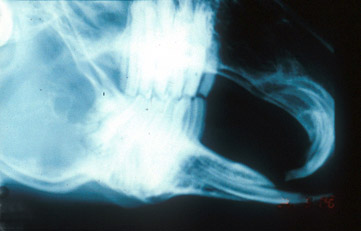

Rabbit right-left lateral with slight

tipping. Note superimposition